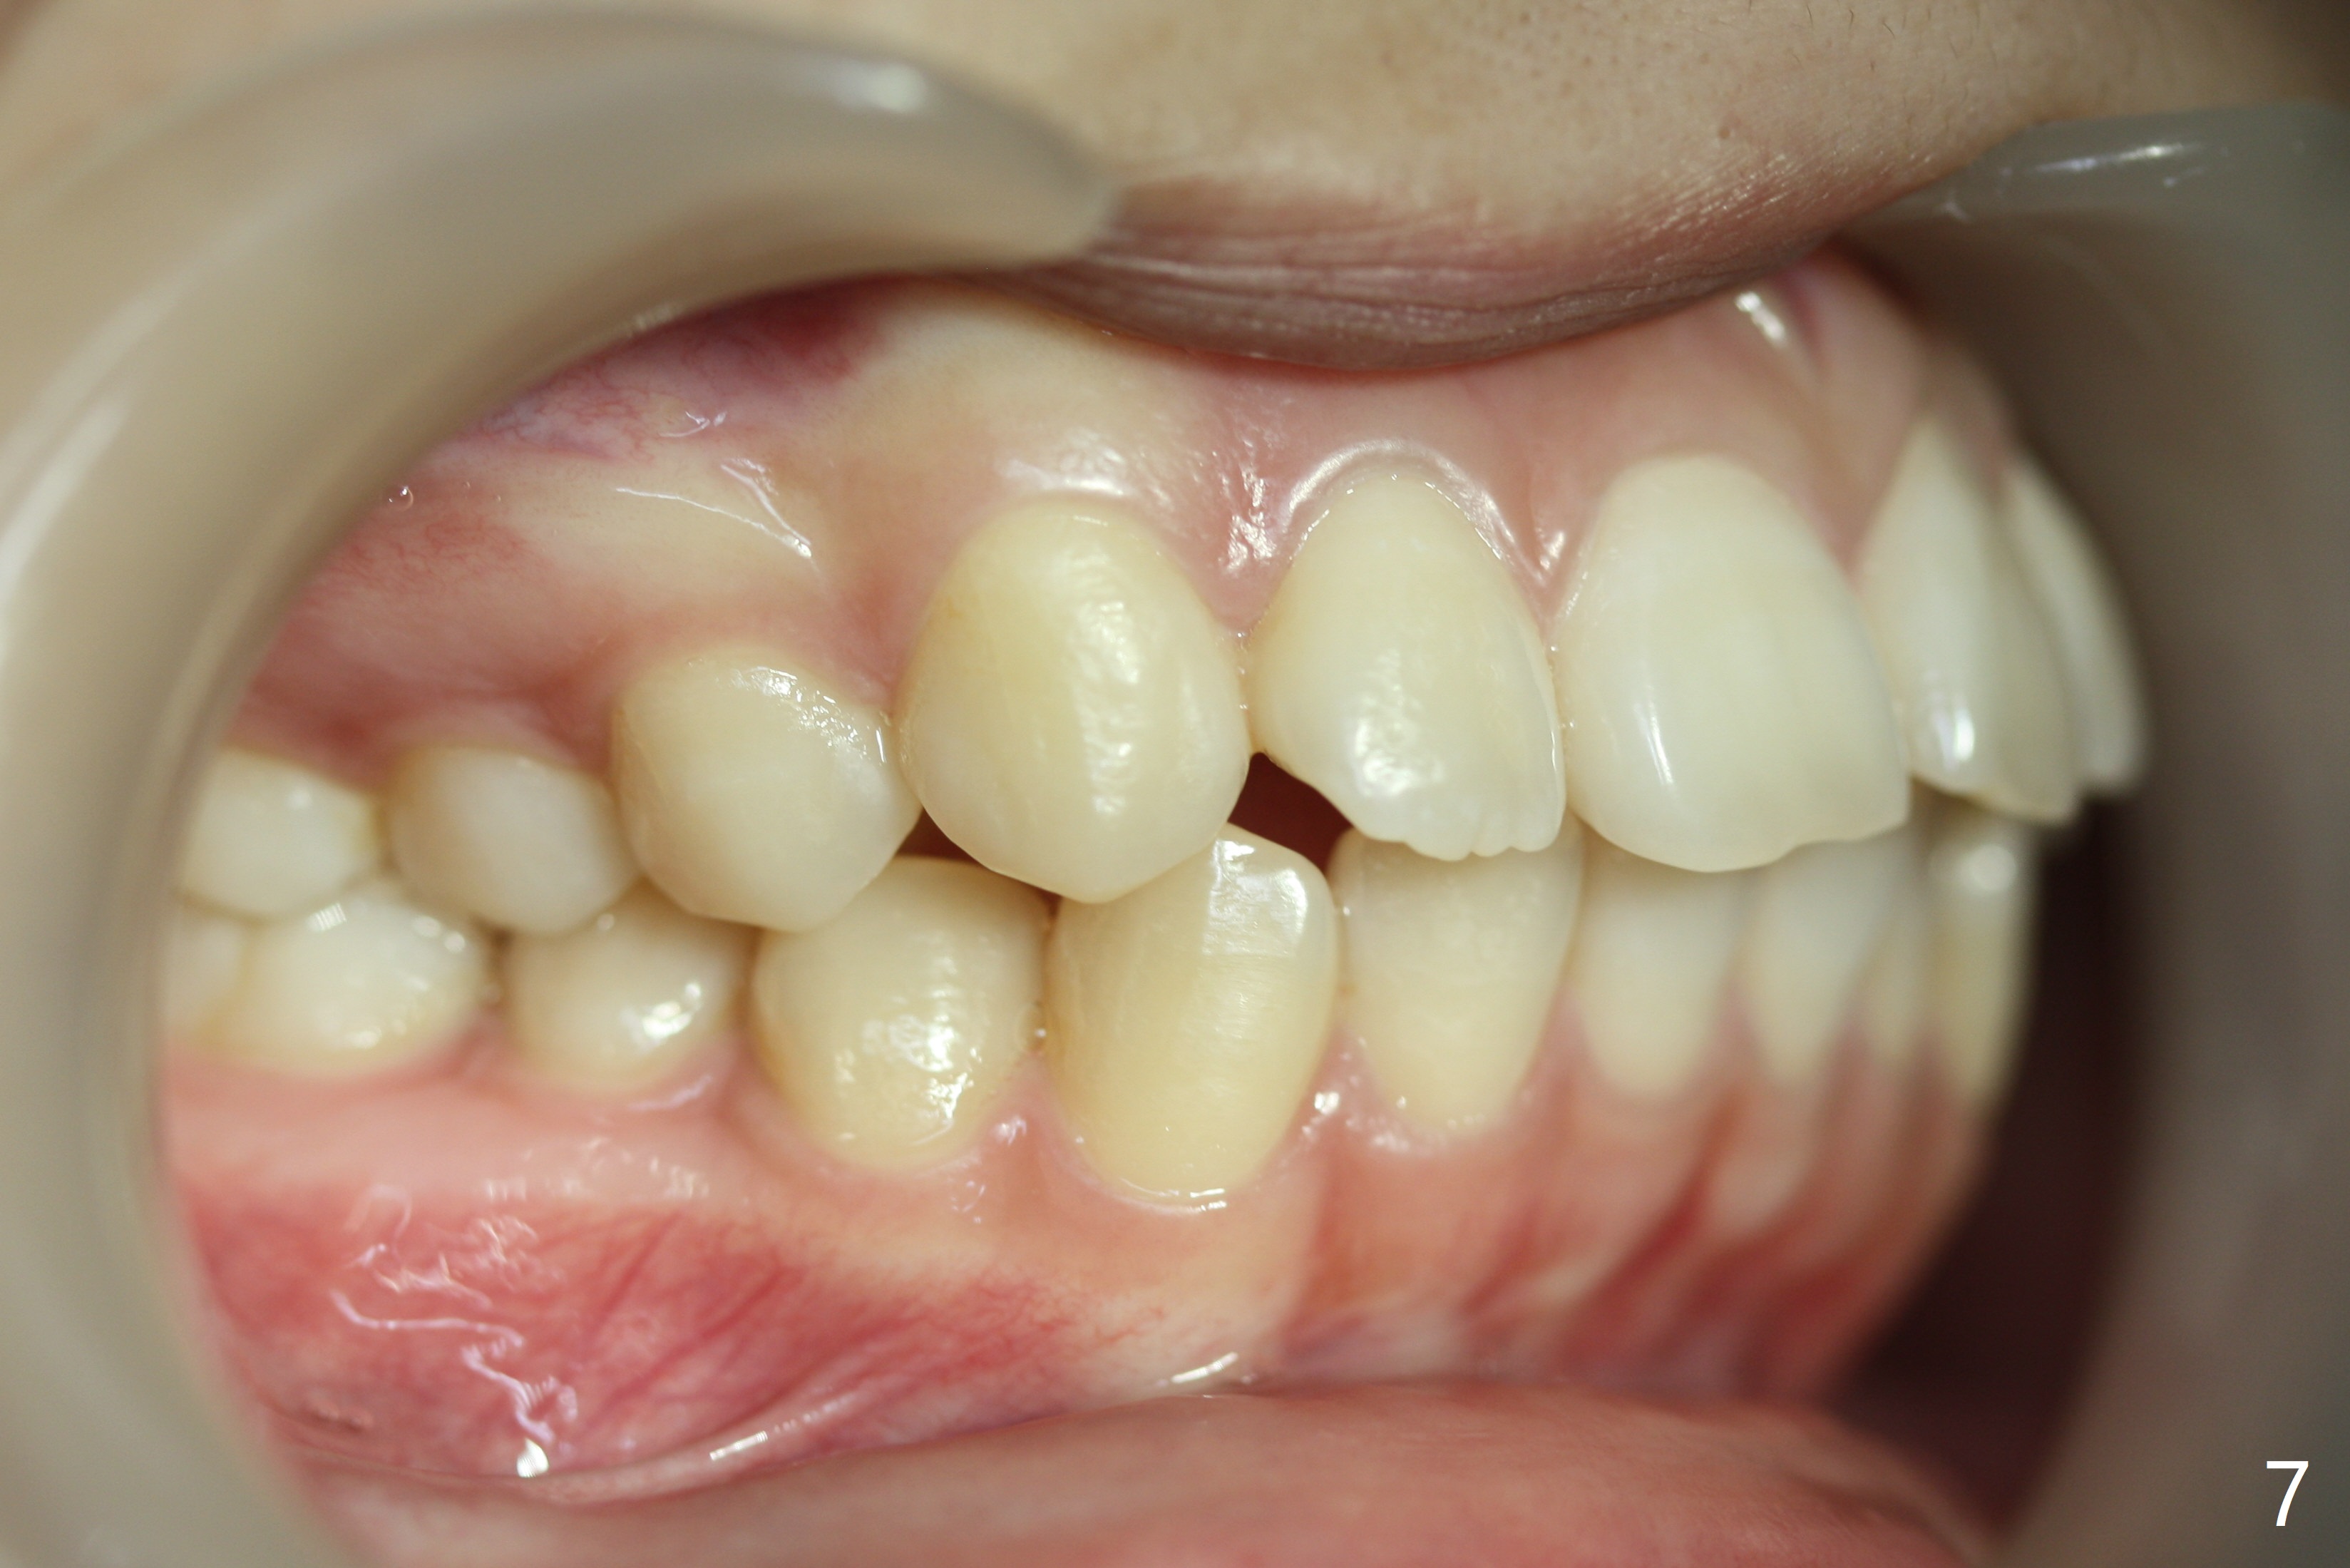

A 15-year-old woman has protrusive lips and retrusive chin (Fig.1-6). Canines and molars have Class I occlusion (Fig.7-9). With 4 bi extraction and 5-7 anchorage (Fig.10-12), 3s will be distalized after 16x16 wires, followed by posted wire retraction of 4 incisors.